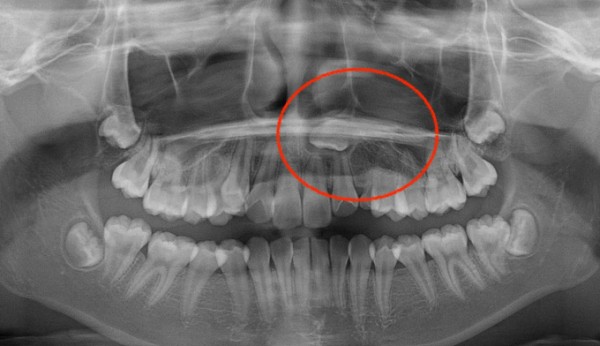

한쪽에는 덧니, 다른 한쪽에는 매복치가 있는 케이스입니다.

매복치의 방향이 수평으로 누워있기 때문에 저절로 구강내로 맹출하지는 못합니다.

따라서 잇몸 절개 후 교정장치를 부착하여 치아를 견인해주어야 합니다.

성인이라면 그냥 무시하고 지낼 수 있지만, 어린나이의 성장기 아이들의 경우에는 교정기간을 투자하는게 긴 인생을 봤을 때 교정치료를 하는게 가치있는 일이라고 생각합니다.